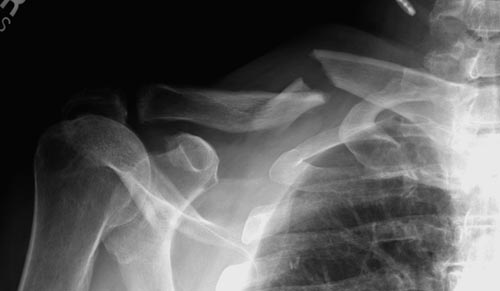

Уважаемые коллеги. Обратился пациент 29лет, оперирован в 2007 г. в Республиканском центре по поводу перелома ключицы и/м спицей, после несращения повторно оперирован в 2008 году, со слов больного освежение и повторно фиксация спицами, и обратился только через 6 лет, активные и пассивные движения в правом плечевом суставе в полном объеме, беспокоит только слабость при поднятии тяжести и подвижность в с/з ключицы. Р-снимок прилагается.Честно признаться, пока не знаю, что делать, имеются обычные пластины из ЦИТО, спицы, может, краевая резекция до появления «росы» дефект заполнить спонгиозной костью, фиксация и/м двумя спицами, загнуть оба конца спицы с компрессей, или пластина…или вообще не трогать. Прощу не критиковать, имеем то, что имеем, пациент в НИИТО не может ехать из-за финансов. С уважением Абдурашид.

Оставлять так однозначно нельзя. Сам по себе ложный сустав не срастется. По поводу спиц думаю, что если с двух попыток не решили проблему, не решат и в третий раз, так как не обеспечивают стабильный остеосинтез.

Краевая резекция до появления "росы", заполнить дефект аутокостью, стабилизировать отломки пластиной с у/с максимально атравматичным способом. На мой взгляд оптимальное решение.